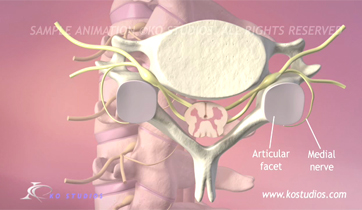

Cervical Facet Syndrome and Rhizotomy

Courtroom Animation for Law firm

This animation was created to be used as demonstrative evidence in a personal injury case. Visual aids such as this can help the jury understand complex medical injuries and procedures. We can customize each animation to be case specific.